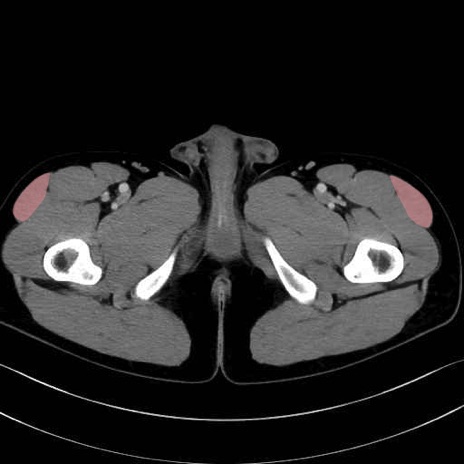

大腿筋膜張筋 (Tensor fasciae latae)